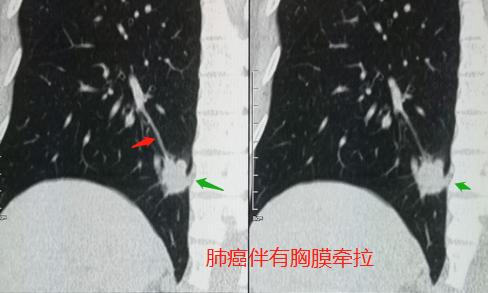

果然发现了右侧肺癌脑转移,伴有胸膜牵拉和增厚。

发现了右下肺癌,伴有肺底部膈胸膜牵拉,符合肺癌并脑多发转移瘤。